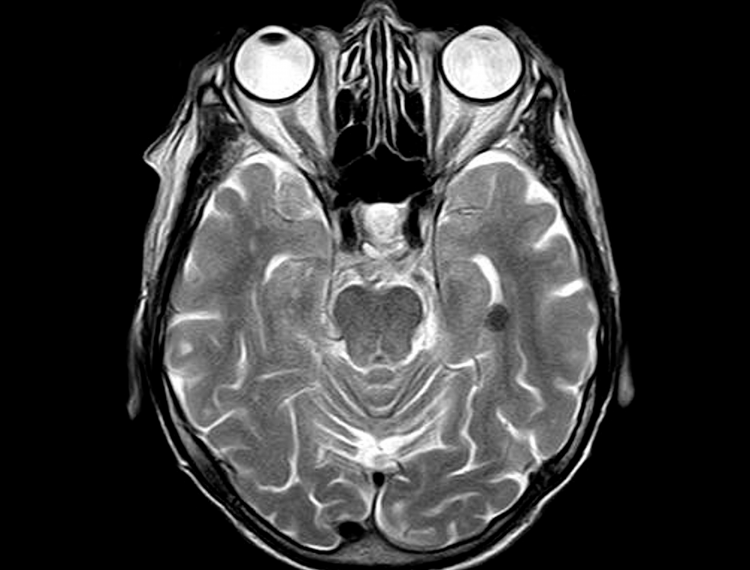

Instabile Kopfgelenke

COVID-19 und CCI/AAI – gehöre ich zur Risikogruppe?

Die kurze Antwort lautet: Definitiv! CCI/AAI, ob ausgelöst durch einen Unfall oder infolge einer Bindegewebserkrankung, schafft es, zahlreiche Schutzvorrichtungen des Organismus gegen krankheitsauslösende Eindringlinge zu drosseln. COVID-19 nimmt also genaugenommen keine Sonderrolle ein.… Weiterlesen